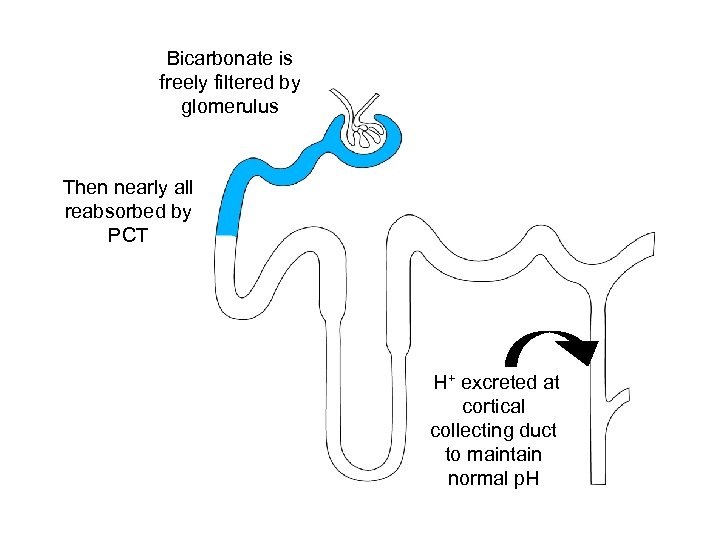

Bicarbonate is freely filtered by glomerulus Then nearly all reabsorbed by PCT H+ excreted at cortical collecting duct to maintain normal p. H

Bicarbonate is freely filtered by glomerulus Then nearly all reabsorbed by PCT H+ excreted at cortical collecting duct to maintain normal p. H